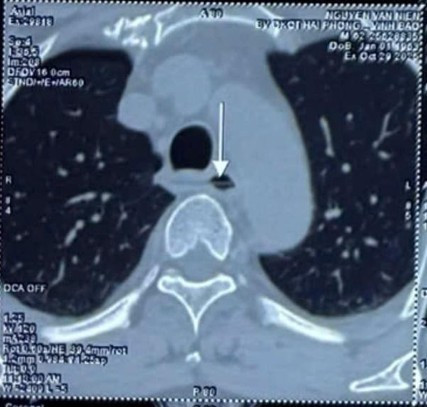

Dị vật xuyên thủng thực quản trên phim chụp - Ảnh BVCC

Khi vào Bệnh viện TWQĐ 108, bác sĩ đánh giá đây là ca nguy cơ rất cao: dị vật sắc nhọn có thể gây suy hô hấp cấp, thậm chí đâm thủng động mạch chủ, dẫn đến sốc mất máu nguy kịch.

Ngay lập tức, bệnh nhân được hội chẩn liên khoa Cấp cứu Tiêu hoá, Ngoại Tiêu hoá, Ngoại Lồng ngực. Kíp y bác sĩ quyết định đặt dẫn lưu màng phổi phải dự phòng, chuẩn bị tình huống xấu nhất và tiến hành nội soi cấp cứu.

Chỉ sau 20 phút thao tác tỉ mỉ, bác sĩ đã gắp thành công dị vật ra ngoài bằng kìm chuyên dụng, theo trục song song thực quản, hạn chế tối đa nguy cơ chảy máu hoặc rơi vào đường thở.

Kiểm tra lại thấy có 2 ổ loét tại vị trí xuyên thủng nhưng không còn chảy máu. Sau theo dõi điều trị, bệnh nhân ổn định và ra viện sau 5 ngày.